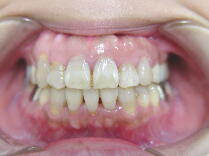

症例1 (10代 女性) 左右上下顎第一小臼歯抜歯例

![]() ![]() ![]()

初診時